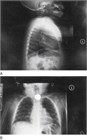

図73.1 胸部と頸部の後前方と側面をあわせたX線写真で上部食道の硬貨が見える.